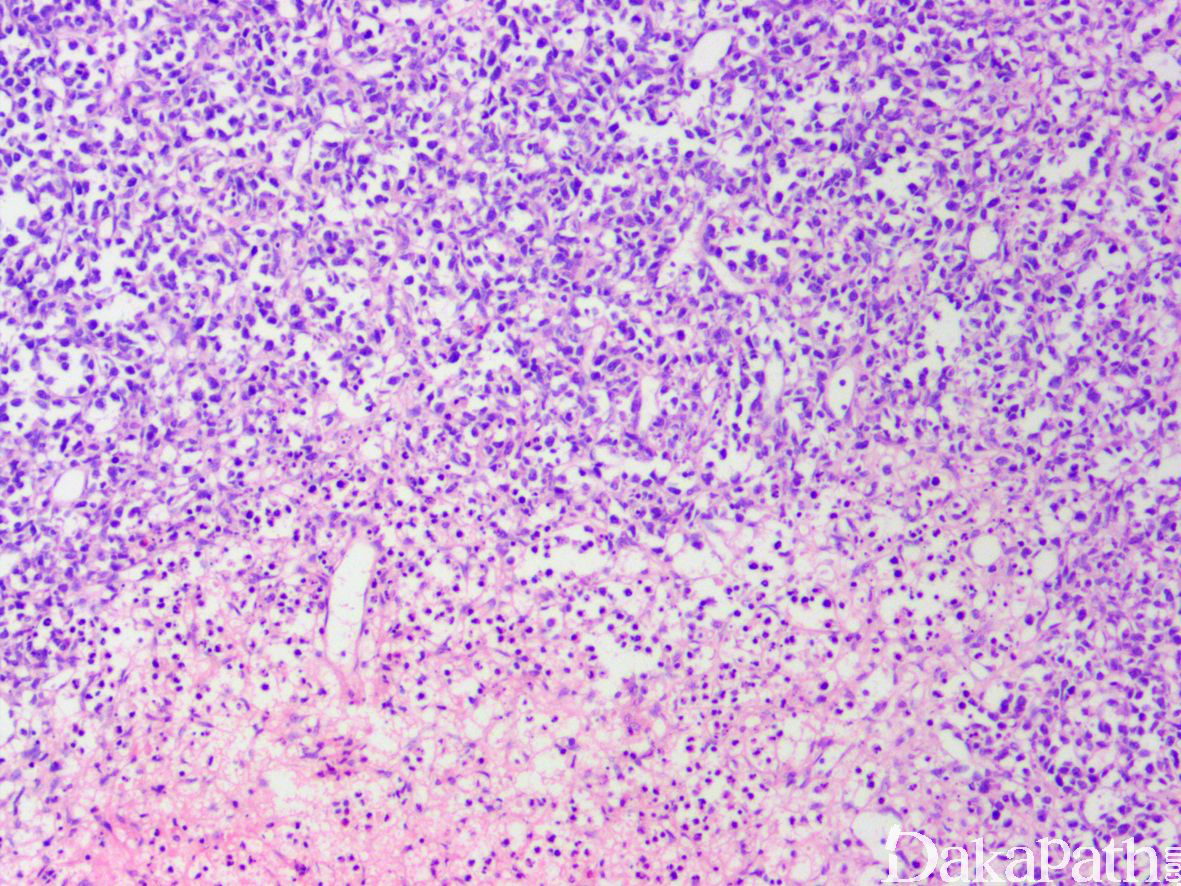

- 镜下异型淋巴细胞弥漫浸润,常见凝固性坏死及细胞凋亡;

- 曲细精管及血管浸润常见,有时可累及附睾;

- 细胞形态及免疫表型同其它部位鼻型结外 NK/T 细胞淋巴瘤,EBV 常阳性。